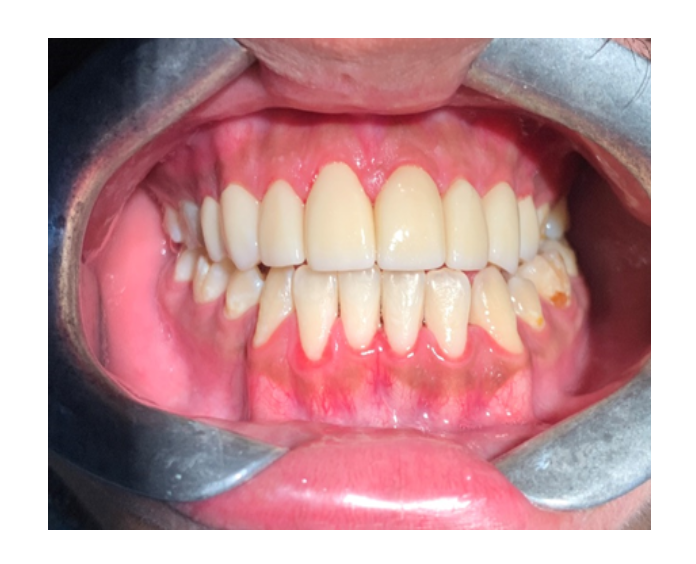

Prótesis fija de zirconia

sin metal